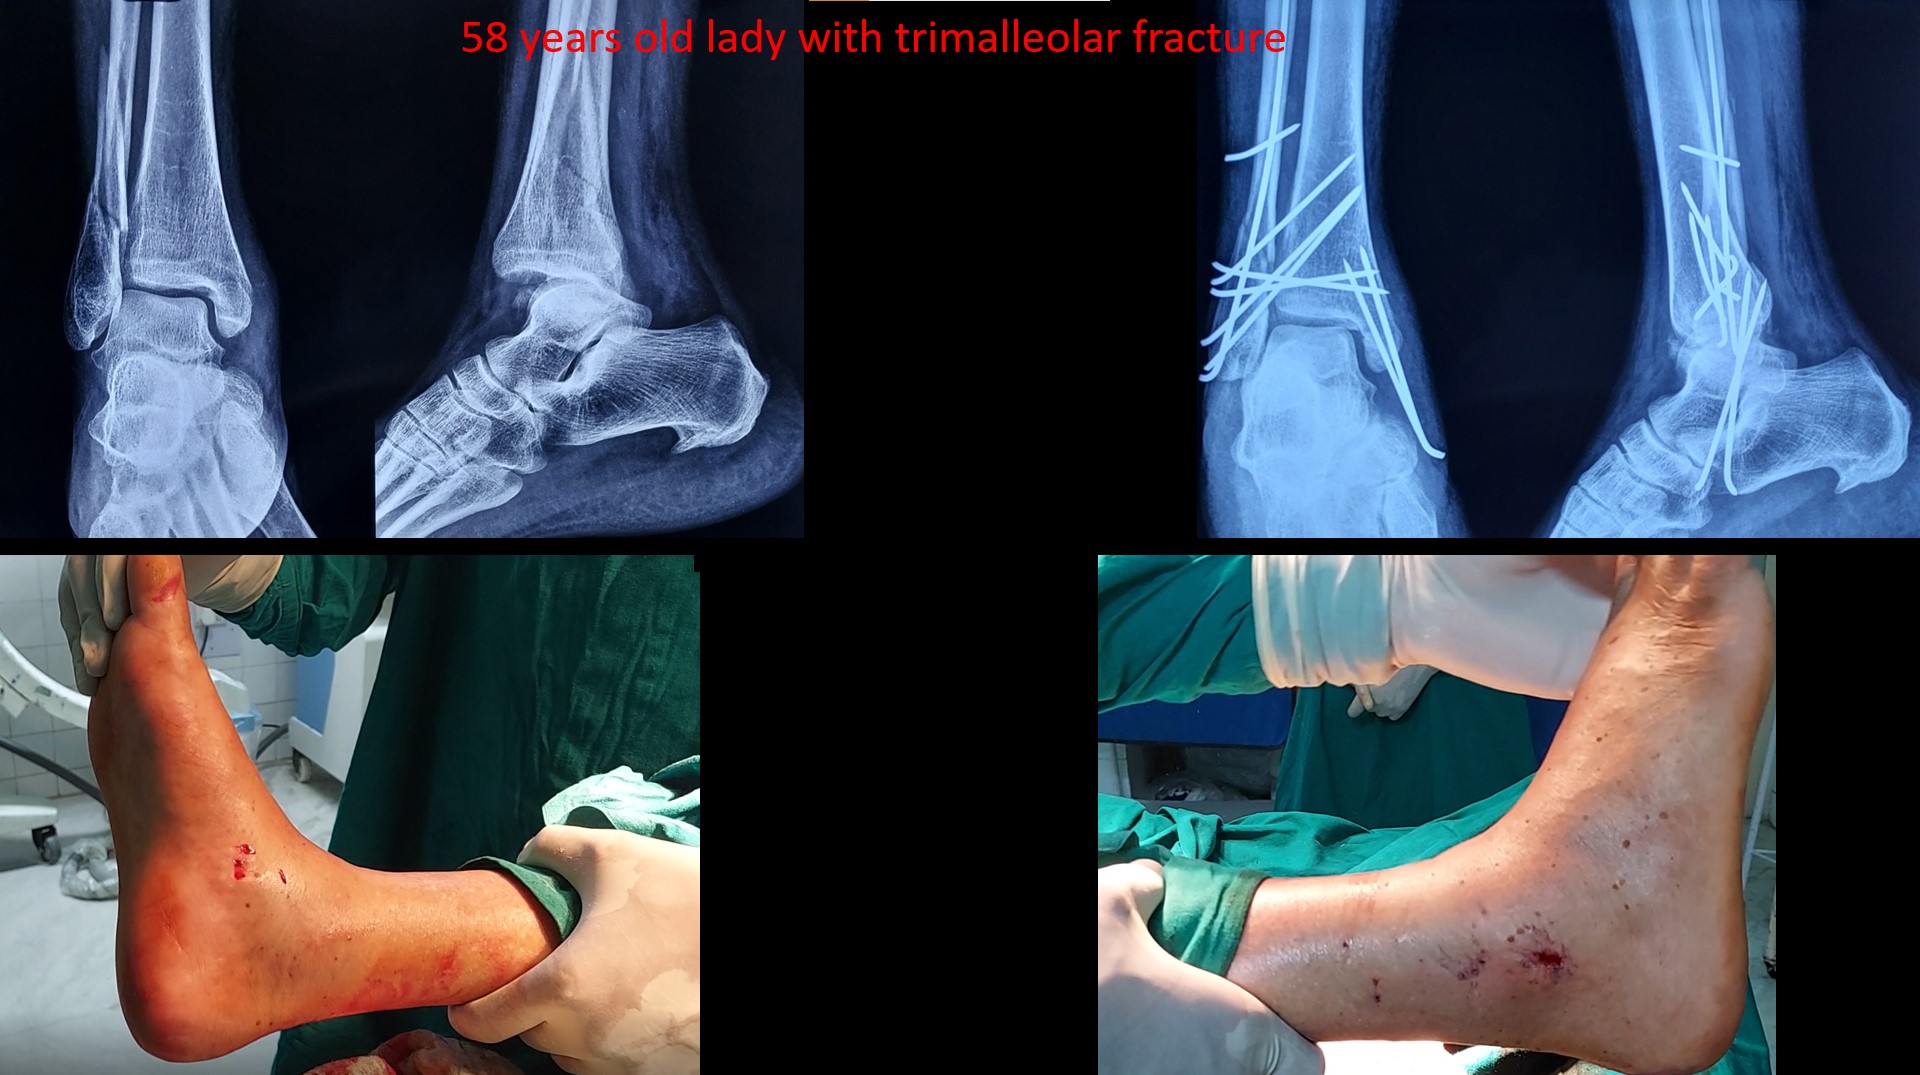

ANKLE